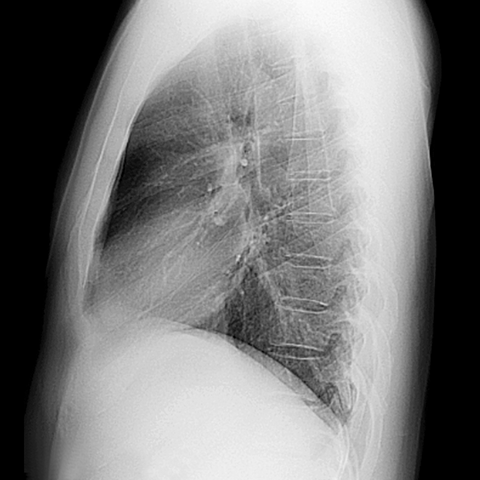

Normal Left Lateral Chest Radiograph [3 of 3]